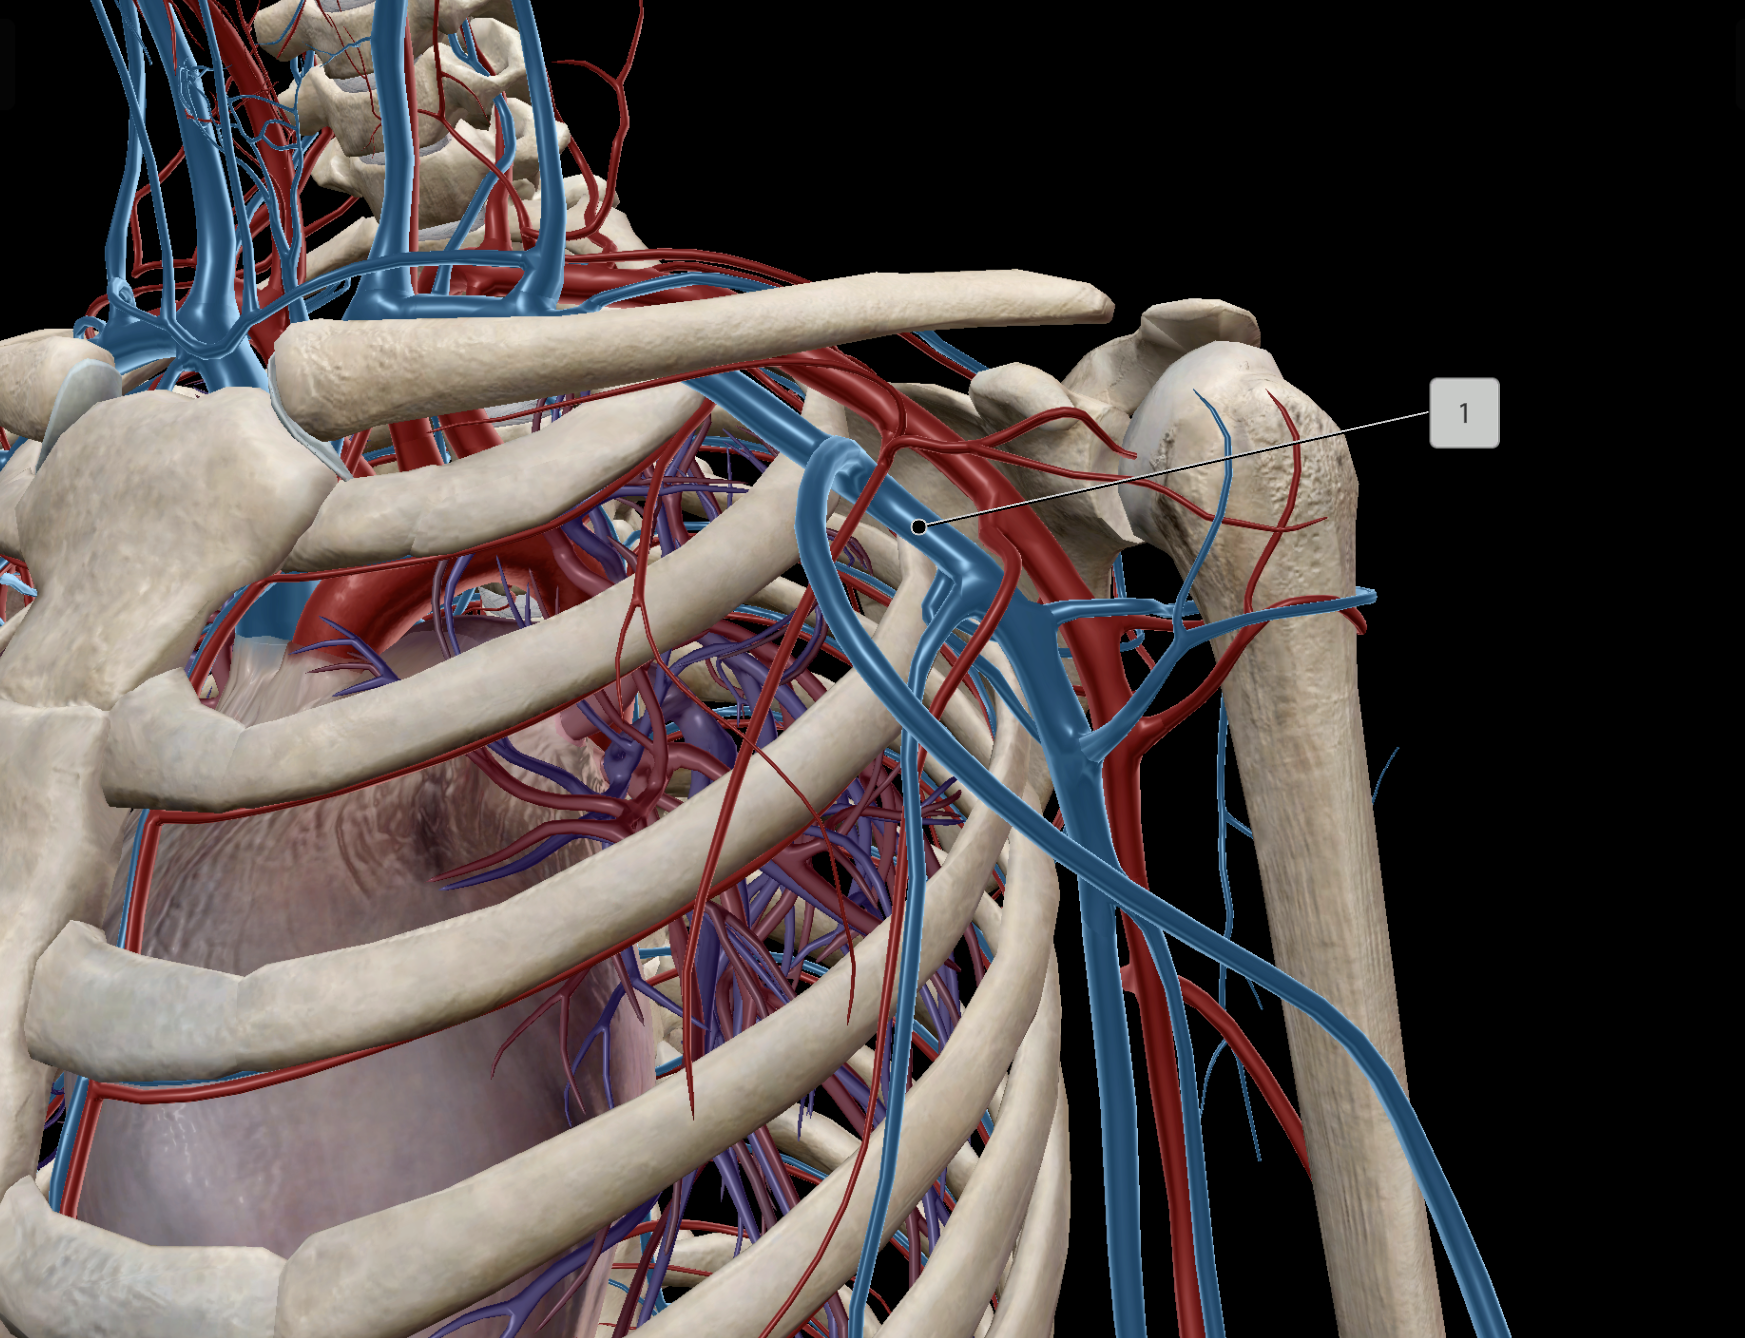

Axillary Artery

Axillary Vein

Subclavian Vein

Subclavian Artery